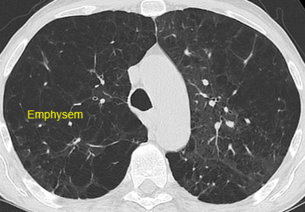

Chronisch obstruktive Lungenerkrankung (COPD) und Emphysem – CT-basierte Beurteilung

Bei der chronisch obstruktiven Lungenerkrankung (COPD) und beim Emphysem kann die Computertomographie (CT) helfen, Ausprägung und Verteilung der Veränderungen zu beurteilen. In geeigneten Fällen unterstützen quantitative Auswertungen die Therapieplanung und Verlaufskontrolle.

Beispielhafte Aufnahmen verschiedener Erkrankungen

(Lungenklinik Lostau)